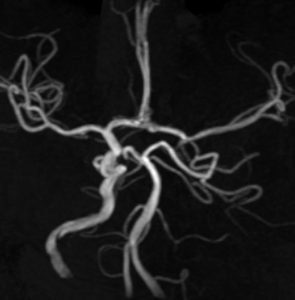

頭蓋底の脊索腫再発のために炭素イオン線 60グレイ16分割の治療を受けました。5年後に両側の側頭葉の脳壊死が生じました。そのために高度の高次脳機能障害となりました。両側の海馬(黄色い矢印)の壊死のために記憶が全くできません。でもしかし,この患者さんは重粒子線治療を受けなければ腫瘍再発で亡くなっていたと私は考えています

左内頸動脈が炭素線被爆したために閉塞しています。

重粒子線は高度の悪性腫瘍をやっつける強力な治療である反面,このように脳や動脈が被爆すればその組織も破壊されてしまいます。悪性腫瘍を破壊できる強力な粒子線治療は,その周囲の神経組織もかまわず破壊する治療であるとも言えます。